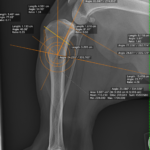

中型サイズのワンコの前十字靭帯断裂にCBLOの依頼です。ドロアーサイン陽性、脛骨圧迫試験陽性、脛骨ピボット圧迫試験陰性、慢性のCrCLDに急性の半月板損傷が併発し、今回の跛行が顕著になった可能性があります。2,7 CCWO PlateとCompression Bone Screwを用いてCBLOを実施しています。しばらくは安静が必要です。